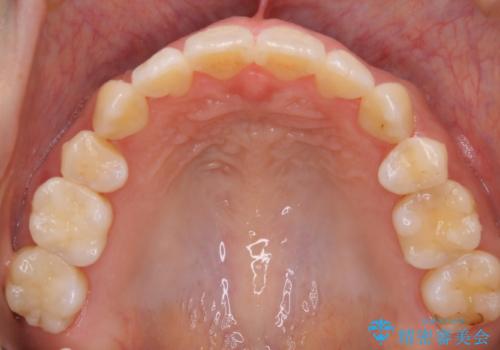

- 前歯のガタつき・噛み合わせの不調を主訴にご来院されました。

患者様のお仕事柄、目立たない装置で矯正したいとのご要望があり、今回はインビザラインを用いて抜歯矯正を行うこととなりました。

本来、抜歯によって得られる大きなスペースのコントロールはワイヤー装置の方が得意とされていますが、こちらの患者様のように犬歯が大きく手前に傾斜していて奥歯の噛み合わせにそれほど問題がないケースではマウスピース装置でも十分にコントロールできることが予測されます。

歯のガタつきの度合いが強い場合や、上下で大きく噛み合わせがズレている時などに、その改善のための大きなスペースを作る代表的手段が「抜歯」です。

一般的には第一小臼歯(犬歯の一つ隣の歯)を抜くことが多く、前歯のガタつきを改善したり口元を引っ込める場合に利用されます。